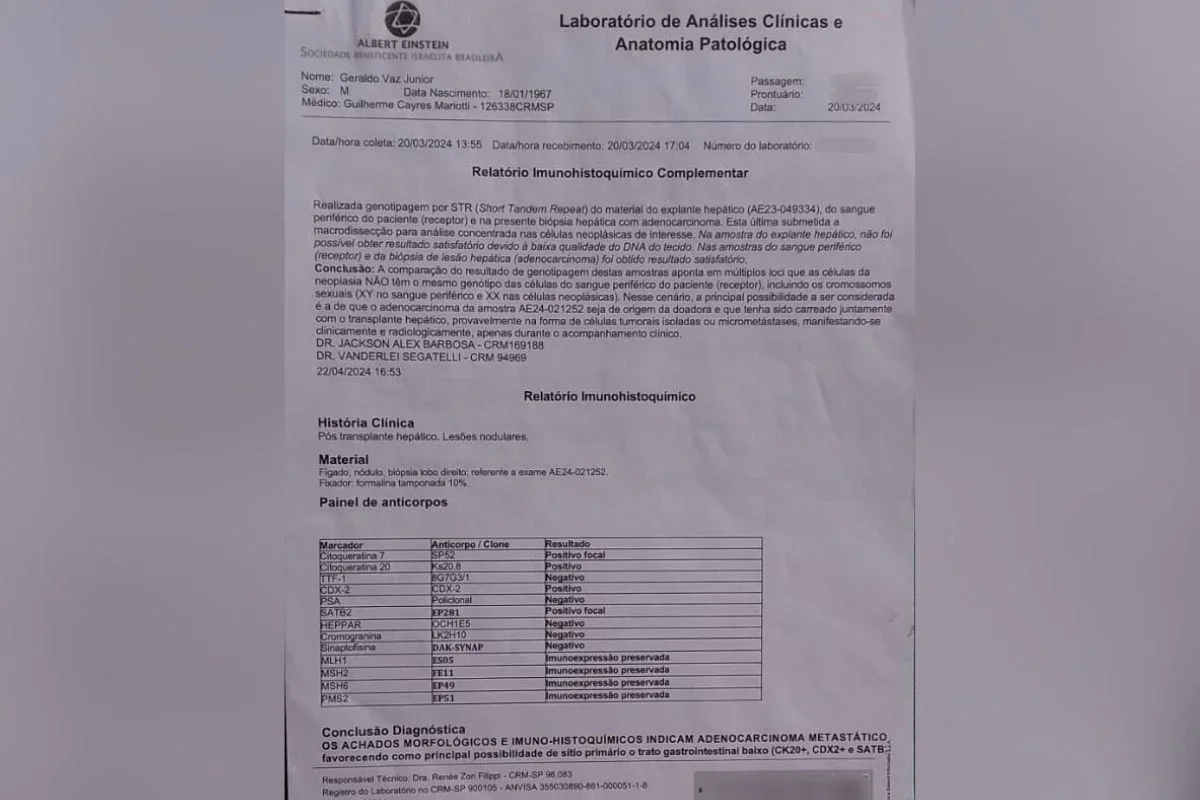

Um exame genético confirmou que o câncer que atinge Geraldo Vaz Junior, de 58 anos, teve origem no fígado que ele recebeu em um transplante feito em julho de 2023. A confirmação veio sete meses depois, quando, em março de 2024, foi descoberto um adenocarcinoma e um teste de DNA indicou que as células tumorais não pertencem ao organismo de Geraldo, mas sim ao doador do órgão.

A análise foi realizada no Hospital Albert Einstein, mesmo local onde o transplante foi feito e onde o paciente atualmente realiza quimioterapia. Em agosto do ano passado, médicos identificaram metástases nos pulmões de Geraldo. O laudo apontou que o tumor foi transmitido com o órgão, possivelmente por células isoladas ou micrometástases que só se manifestaram posteriormente.

A médica Caroline Daitx, especialista em medicina legal, avaliou os documentos e afirmou que o resultado do DNA é conclusivo. Segundo ela, o tumor apresenta cromossomos XX, típicos de uma mulher, enquanto Geraldo possui XY, o que comprova que o câncer veio da doadora do fígado. O Ministério da Saúde, inicialmente, negou relação entre o transplante e o câncer, mas depois reconheceu que os exames do doador não mostraram sinais de doença e que os protocolos foram seguidos.